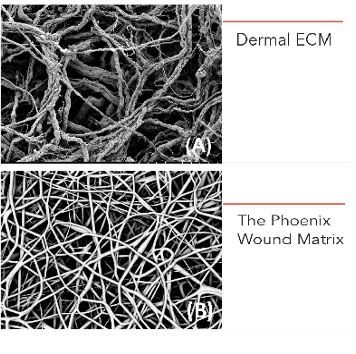

- The Phoenix Wound Matrix®, a fully resorbable, 3D electrospun device composed of synthetic polymers, is designed to provide a temporary microenvironment that supports endogenous wound healing, allowing for regeneration and remodeling of native tissue in the defect space/wound bed. This device is engineered to promote healthy tissue growth rather than a protracted inflammatory response.†

- For over a decade, Nanofiber Solutions, the technical parent company of RenovoDerm®, has worked with progressive surgeons and researchers to develop products designed to mimic the in vivo, microscopic, physical structures and properties of the extracellular matrix (ECM) vital to functional tissue regeneration.

- The Phoenix Wound Matrix®, a fully resorbable, 3D electrospun device composed of synthetic polymers, is designed to provide a temporary microenvironment that supports endogenous wound healing, allowing for regeneration and remodeling of native tissue in the defect space/wound bed. This device is engineered to promote healthy tissue growth rather than a protracted inflammatory response.†

- For over a decade, Nanofiber Solutions, the technical parent company of RenovoDerm®, has worked with progressive surgeons and researchers to develop products designed to mimic the in vivo, microscopic, physical structures and properties of the extracellular matrix (ECM) vital to functional tissue regeneration.